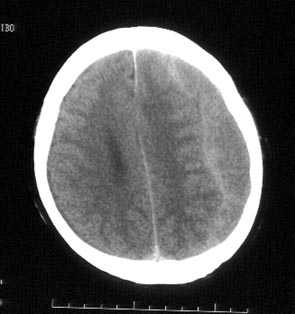

病史:男性,56岁,自觉右侧肢体肌力下降,伴麻木不适半月,逐渐加重。一个月前曾有头部轻微碰伤史,但具体经过不能回忆。

ct平扫:左额及颞顶叶见新月形略高密度血肿影,左右及前后径为2.5x12.7cm。左侧脑室受压变形右移,中线右偏约1.2cm,且密度增高,鞍上池闭塞,中脑受压变形。

ct诊断:左额、颞、顶部慢性硬膜下。